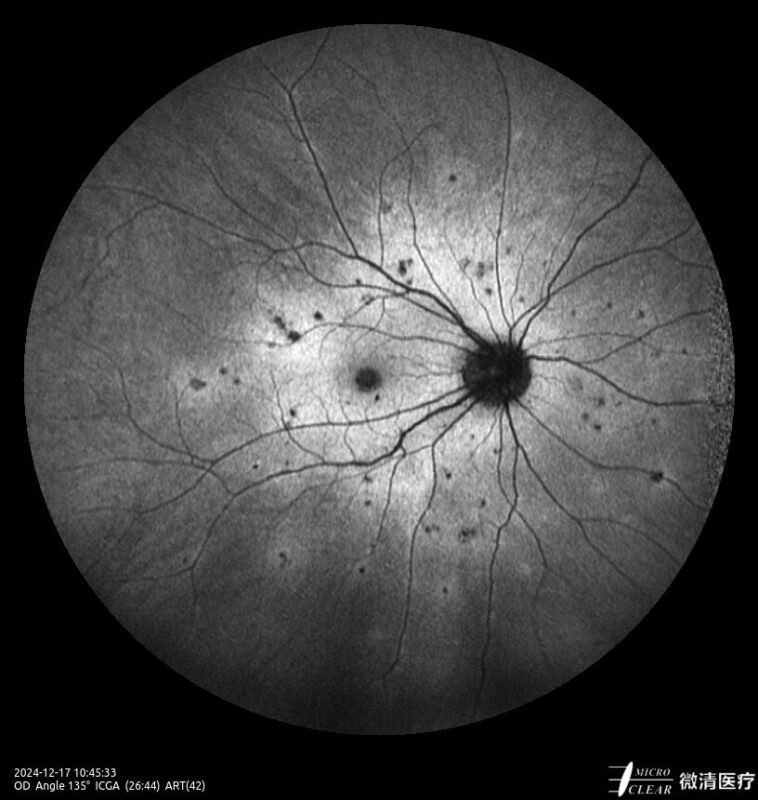

Ultra-groothoek en multimodale fundusangiografie gebaseerd op confocale scanning laser oftalmoscopie (CSLO).

- Fundusfluoresceïne-angiografie (FFA)

- 135° WA (Groothoekangiografie) – in één opname

Confocale Scanning Laser Oftalmoscoop (CSLO)

- Combinatie van drie confocale laserbronnen voor maximaal contrast en getrouwheid.

- Verbeterd confocaal ontwerp zorgt voor een betere scheiding van de netvlieslagen en verbeterde penetratie door cataract en oculaire troebelingen.